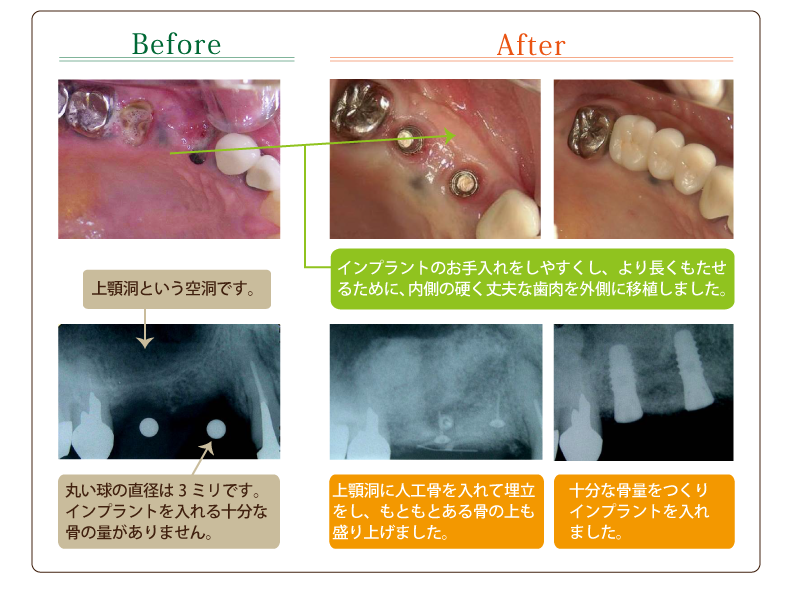

[ CASE1 ] インプラントとインプラント周囲の骨造成および歯肉移植等を用いて咬合再構成を行ったケース

[ CASE3 ] 骨造成を行いインプラントを埋入しインプラント周囲に歯肉移植を行ったケース